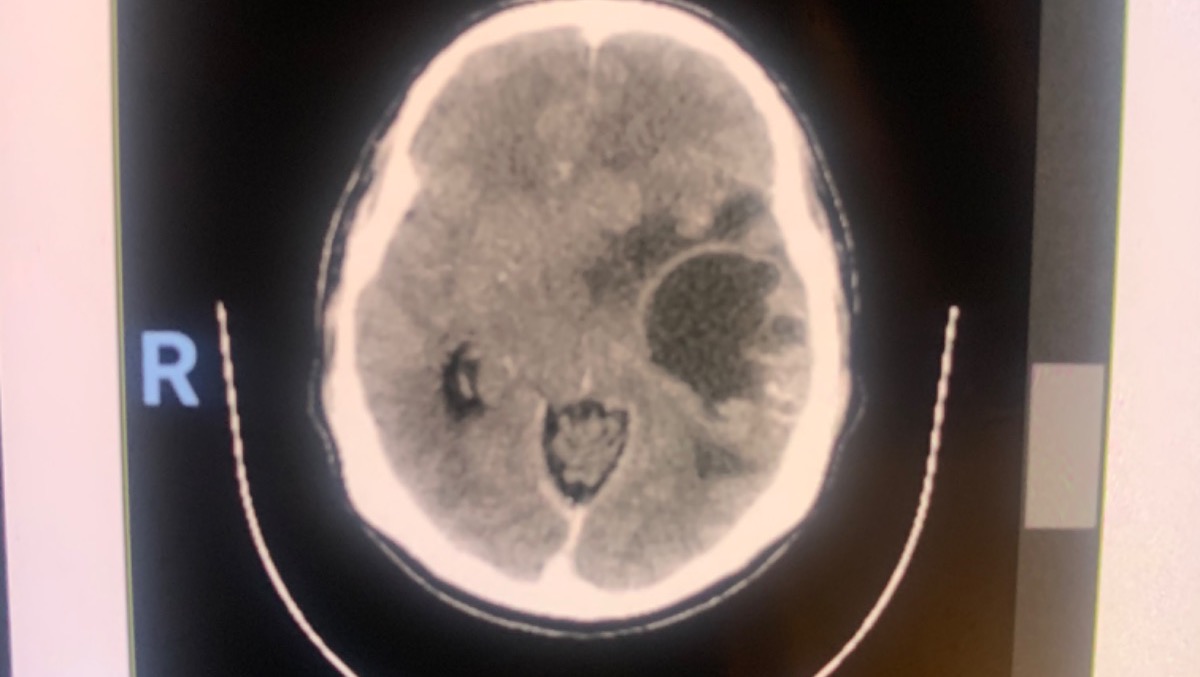

Update: our dad has a big brain tumor. He’ll have surgery as soon as we have the money. The surgery will be around $15,000 US dollars.

Actualización: nuestro papá tiene un tumor cerebral muy grande. Va a tener cirugía en cuanto juntemos el dinero. La cirugía costará alrededor de $15,000 dólares.